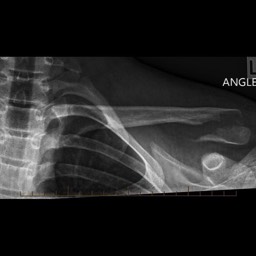

What do clavicle fractures look like on X-ray?

Below are examples of typical fractures that benefit from surgery.

Click an image to enlarge